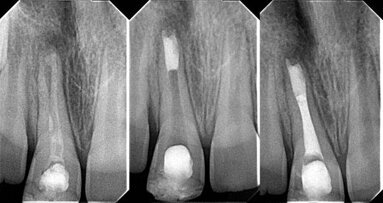

The AC was located radiographically by advancing the #15 K file until its tip was 1 mm from the radiographic apex (determined from a pretreatment parallel technique radiograph). A radiograph was exposed, and if the file tip was seen not to be 1 mm from the radiographic apex the file was repositioned and another radiograph taken to ensure that it was. The distance from the stop to the tip was the insertion length. The file was then reinserted to the insertion length (1 mm from the radiographic apex) and cemented in place with GC Fuji II LC dual-cure glass ionomer cement (GC Corporation). The file handle was sectioned with a high-speed bur, and the tooth was extracted without disturbing the file by an experienced oral surgeon, immersed in 2.5% NaOCl for 30 minutes to remove any residual organic tissue from the root, and then kept in a 1% thymol solution in a numbered specimen cup.

The apical 5 mm of the root was clipped in a longitudinal direction using a fine, flat cylinder diamond bur (Brasseler) under a stereomicroscope (Zeiss Stemi 2000-C, Carl Zeiss) at 16x magnification to expose the file tip.

The remaining tooth structure was removed carefully until the file tip and the root canal were both visible. A digital photograph was taken and stored in Adobe Photoshop 5.5 (Adobe Systems), and the distance from the file tip to the minor foramen was measured using Image Tool 3.1 software (University of Tennessee Health Science Center).

The distance from the file tip to the AC was measured. This distance was recorded as being (a) -1 mm from the AC; (b) -0.5 mm from the AC; (c) at the AC; (d) +0.5 mm from the AC; and (e) +1 mm from the AC. A minus symbol (-) indicated a file short of the AC, and a plus symbol (+) indicated that it was beyond the AC.

The position of the file tip in each root canal was evaluated by two examiners. If the two examiners disagreed, a third previously calibrated researcher was asked to make the final decision. The final WL was established to be 0.5 mm coronal to the major foramen.24 Once the actual length to the AC had been measured visually, the distance from the AC determined by the four EALs was also calculated (-1 mm from the AC, -0.5 mm from the AC, etc.), by comparing their insertion lengths to the actual length (i.e. distance to the AC; Tables 2 & 3).